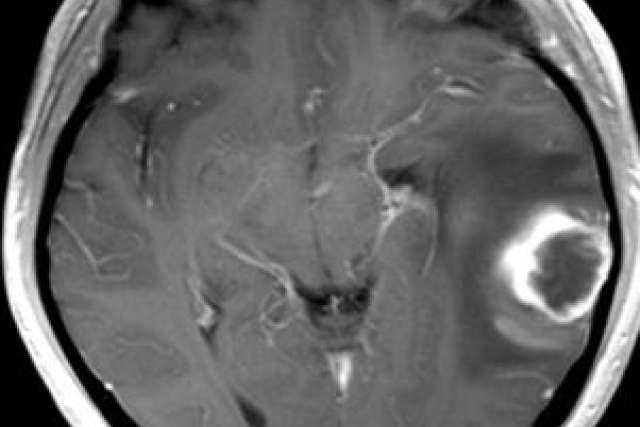

The UCLA team studied 82 patients who had undergone surgery and radiation therapy to remove glioblastoma. Half of the patients received infusions of Avastin every two weeks. All underwent monthly brain scans by magnetic resonance imaging (MRI) to monitor change.

The researchers analyzed the MRI scans of the patients whose tumors returned. Explaining what the team saw requires an understanding of how the tumor creates an independent blood supply.

This process launches a chain of events that is detectable by MRI. Oxygen-starved cells produce more VEGF, which causes blood vessels to leak fluids into the tumor and surrounding tissue. This results in swelling, which boosts water's ability to move freely in the tumor and brain tissue. As cells disintegrate, they no longer pose a physical barrier to water movement.

By measuring the amount of water motion within the tumor, the researchers were able to predict with 70 percent accuracy which patients' tumors would progress within six months and which would not. They detected greater water movement in the tumors of those persons who later responded best to Avastin.